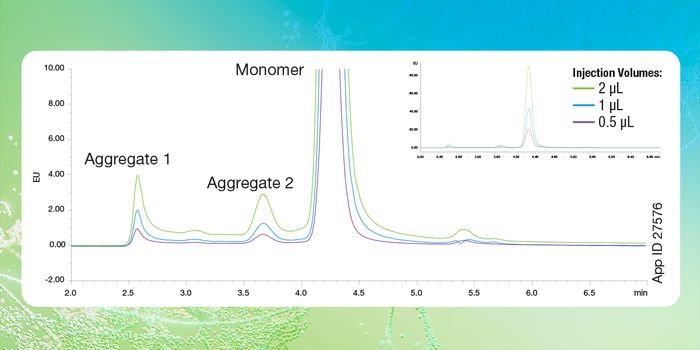

JUN 18, 2024Drug Discovery & DevelopmentSEC is a chromatographic technique that separates various analytes in a sample based on their hydrodynamic radius. It is ...